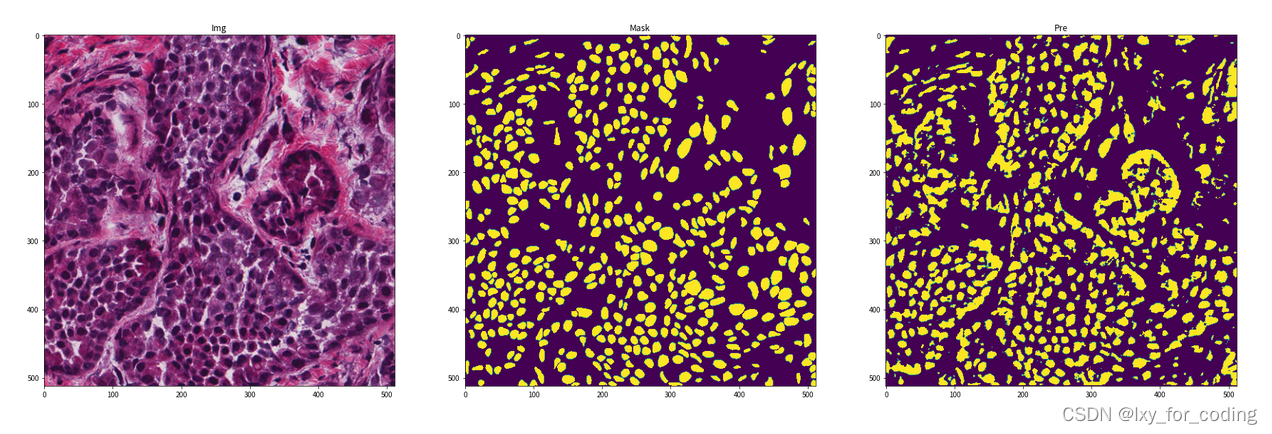

step5:模型预测及评估

step6:可视化展示

img = img.mul(255).byte().squeeze().numpy().transpose((1, 2, 0))

print("img.shape={}, mask.shape={}, pre.shape={}".format(img.shape, mask.shape, pre.shape))

fig, ax = plt.subplots(1, 3, figsize=(30, 10))

ax[0].imshow(img)

ax[0].set_title('Img')

ax[1].imshow(mask)

ax[1].set_title('Mask')

ax[2].imshow(pre)

ax[2].set_title('Pre')

在我们探索这个 U-net 细胞分割项目的过程中,我们深入了解了在生物医学图像分析领域中的重要应用。通过这个项目,我们更加理解了 U-net 这一强大的语义分割方法,它能够精确地提取细胞图像中的像素点,为生物医学领域的研究和诊断提供了重要支持。

此外,我们还通过示例代码演示了如何加载和预处理数据集,构建 U-net 模型,并对其进行训练和预测。通过详细的代码注释,我们希望能让你更容易理解每个步骤的目的和功能。最后,我们展示了一些图像示例,向你展示了 U-net 分割模型的效果。